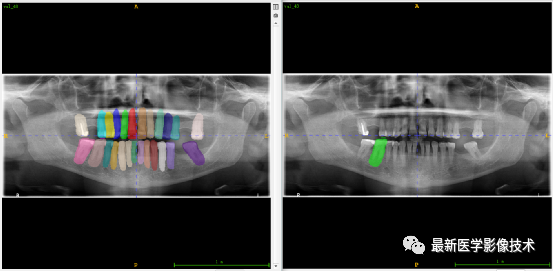

验证集牙齿分割计数和异常牙齿分割识别

左图是分割计数,右图是异常牙齿分割识别结果